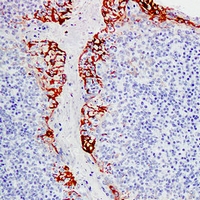

Mouse anti-MUC1 Monoclonal Antibody

PUM; Mucin-1; MUC-1; Breast carcinoma-associated antigen DF3; Cancer antigen 15-3; CA 15-3; Carcinoma-associated mucin; Episialin; H23AG; Krebs von den Lungen-6; KL-6; PEMT; Peanut-reactive urinary mucin; Polymorphic epithelial mucin; PEM; Tumor-associated epithelial membrane antigen; EMA; Tumor-associated mucin; CD227,MUC1

WB, IHC